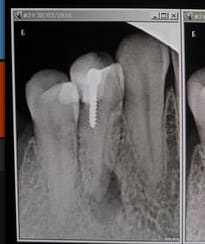

26/04/2016 à 14h31

Je ne comprends pas, pourtant j'avais tout mis en oeuvre pour faire cette superbe endo tarif sécu de merde ! -)

Capture d e cran 2016 04 26 12.30 - Eugenol